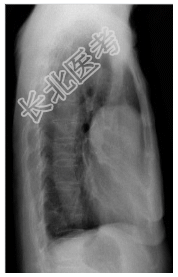

- [材料题] 患者,女性,55岁,重症肌无力多年,发现贫血1年余。查体.双侧眼睑下垂,面色苍白。行胸部平片检查。

- 简答题1、诊断及依据是什么?

- 简答题2、鉴别诊断有哪些?